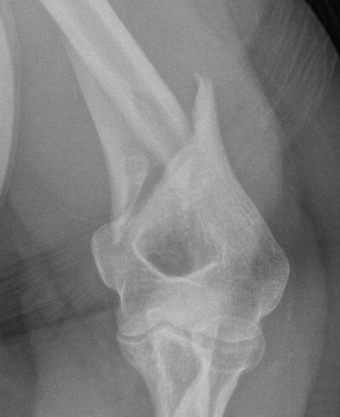

Holstein Lewis / distal humerus fracture